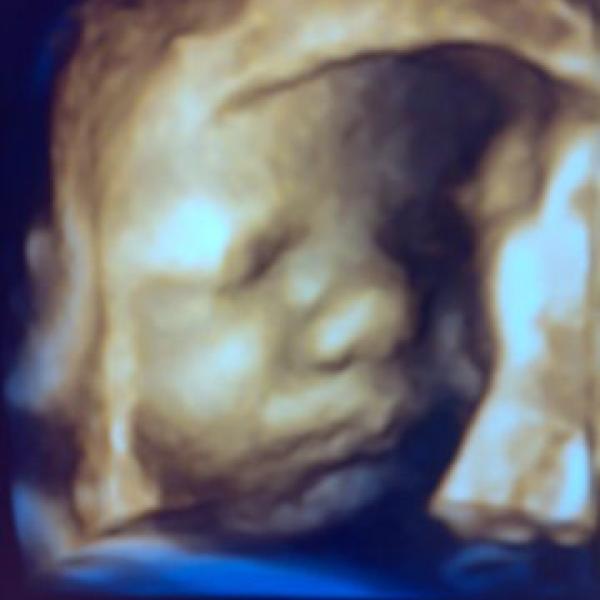

Ahoj tety. Máme dnes za sebou první kontrolu u pana doktora a všechno je v pořádku.

Ahojky maminky a těhulky, tak se Vám hlásíme z domova už i s tím naším malým štěstíčkem. Jak jsem psala v pondělí 15.11., měla jsem ráno v 8 hod nástup na vyvolání.